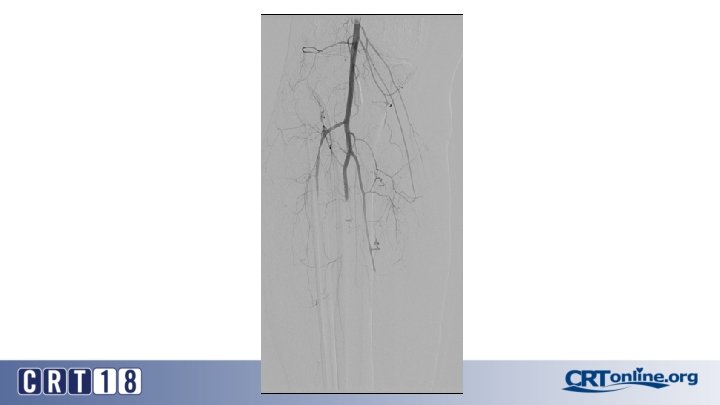

CS Compared to BMS in iliac occlusion • 2009 and December 2015, 128 iliac artery occlusions were stented • A CS was implanted in 78 iliac arteries (61%) and a BMS in 50 (49%) • After propensity score matching (lesion site and length separated and associated femoropopliteal disease included) (47 for each group). • Technical success was 98% • Complication rates same: 12% vs. 12%, p = 1. 0 • 30 day mortality rates same: 2% vs. 2%, p = 1. 0 Piazza M, et al. Outcomes of polytetrafluoroethylene-covered stent versus bare-metal stent in the primary treatment of severe iliac artery obstructive lesions. J Vasc Surg. 2015; 62(5): 1210 -8.

CS superior to BMS, in the right setting • At 36 months (average 23 ± 17) overall primary patency only approached significance: 87% vs. 66%, p =. 06 • For TASC D, CS: 88% vs. BMS: 54% (p =. 03) • Patency was in favor of CSs for occlusions > 3. 5 cm in length (p =. 04), total lesion length > 6 cm (p =. 04), and occlusion with calcification > 75% of the arterial wall circumference (p =. 01) • Kissing stent patency also superior with CS